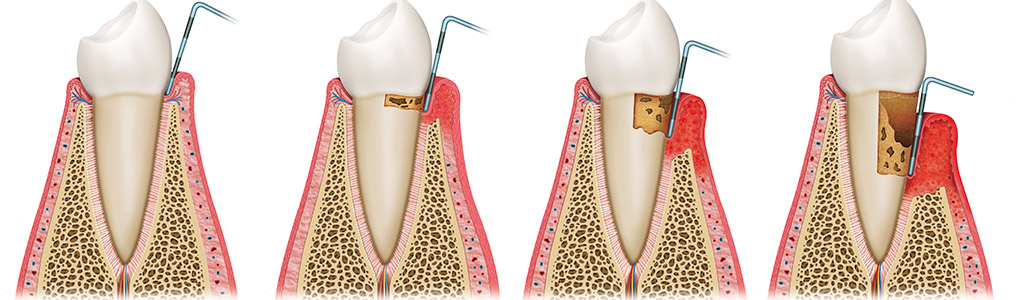

健康的牙齒跟牙齦幾乎是緊密貼合的。牙醫師會使用有刻度的牙周探針,針對每一顆牙齒進行探測檢查,沿著牙面弧度提放式行走,紀錄每一顆牙齒的牙周狀態。健康的牙周狀態,以探針探測,深度介於1-3mm之間,通常不會有滲血狀態出現,而是否有「探測時出血」,是牙齦健康的重要指標之一。當結石形成,發炎的現象越來越嚴重,患有牙周病的牙齒,探測深度會大於3mm,也就是進一步形成牙周囊袋,並且會逐漸加深。由於牙周病菌具有厭氧特性,氧氣較少的牙周囊袋正好成為孕育牙周病的溫床。牙周病菌不斷增生,散發出毒素,並且引發宿主免疫反應,造成齒槽骨吸收。當齒槽骨高度下降,便降低了對牙齒的支持力。如果置之不理、沒有妥善治療,經常導致牙齒喪失或需要拔除。

牙周病的發展階段

了解與牙周病的發展,也可幫助民眾做簡單的自我檢查,以便早期發現、早期治療。健康的牙齦組織為但淡粉紅色,牙齦結實。一旦牙菌斑累積,初期會引發牙齦炎,此時牙齦外觀紅腫,刷牙時牙齦會出血。當牙齦發炎沒有即時控制治療,牙齦炎將發展至牙周病,病患會發現牙齦明顯退縮、牙縫越來越大、牙齒開始對冷熱酸痛敏感、口臭、牙齒搖動,咀嚼時不如以往紮實有力,甚至會有疼痛感,嚴重者口內會出現化膿現象。